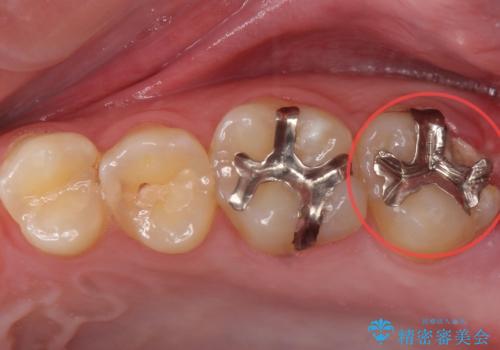

歯のガタつきも解消することができました。

e-maxクラウンでは仮着ができませんが、今回は一回でご満足いただける修復ができました。